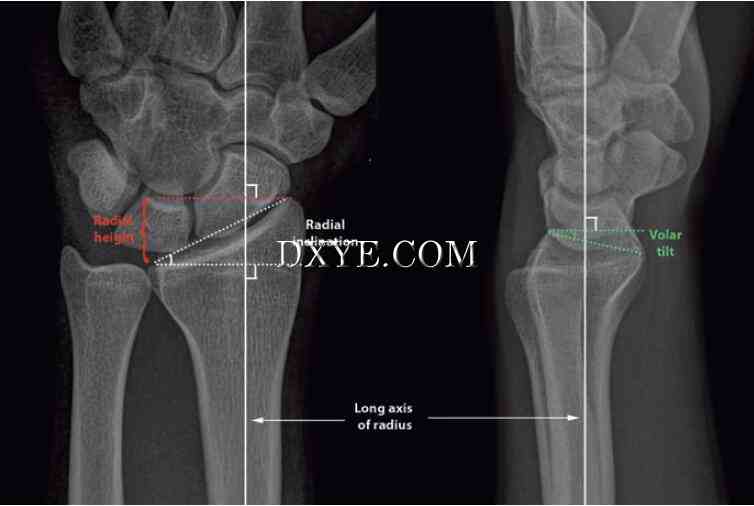

外部固定。外固定器通过将骨折固定到长度并中和骨折部位的压缩,弯曲和扭转力来起作用。对于高度不稳定的骨折伴显著干骺端粉碎的患者,外固定是有用的,因为它们可以使关节面与桡骨干对齐(图76.14)。然而,它们不能用于减少移位的关节内骨折。此技术在感染风险高或明显水肿排除安全切开复位内固定(ORIF)的情况下也是有用的。它通常与K线一起用于其他形式的固定。许多不同类型的外固定器框架可用于不同的针位置,不同的平面刚度,调整骨折复位的能力,以及固定器框架是否跨越桡腕关节(桥接与非桥接)。在桥接外固定器时,一组销钉放置在第二掌骨中,另一组放在近端径向轴中,从而跨越桡腕关节。在非桥接的外固定器中,远侧的销钉组被放置在远侧桡骨的关节片段中。这种设计可以防止韧带过度僵硬和手腕固定。然而,大的和稳定的远端碎片对于放置销是必需的。外固定器框架的变体是经皮放置的背侧固定器板(桥板),其从桡骨骨干延伸至第二或第三掌骨。这种“固定器 - 内部”在多发伤患者中特别有用,因为外固定使护理困难。

图 76.14.  外固定结合经皮穿针置入多发创伤患者,桡骨远端粉碎性骨折(AO C3型)。